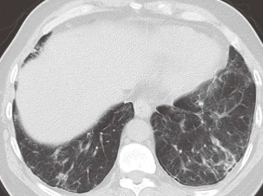

很多人不理解,为什么感染了病毒,肺会变白呢?其实,肺变白是对胸片或胸部CT等影像学检查结果的比较直白的描述。

CT或者X光片的影像,就像黑白照片一样,只有三种颜色,黑、白、灰。不同的颜色代表的不是器官的真实颜色,而是指器官不同部位对X线的吸收能力。

我们肺泡组织中含气量多,肺充分膨胀,X线就能很容易的穿过肺组织,在胶片上体现出来的就是黑色。

当肺部出现炎症反应时,会有大量炎症介质、蛋白质、组织液、白细胞等等渗出,肺间质也会出现充血及水肿,这时的肺组织对X线的吸收能力就明显增强了,有点像实质器官的表现,所以呈现出白色,就叫大白肺。